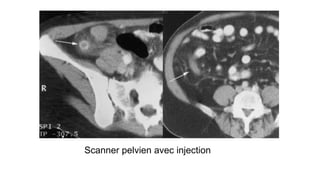

Scanner pelvien avec injection

Stercolithe

Infiltration de la graisse

Épaississement

Appendicite pelvienne en TDM

29 ans , appendicite ?

Hyperleucocytose :15000

Dia: Thrombose phlébite de la veine ovarique droite